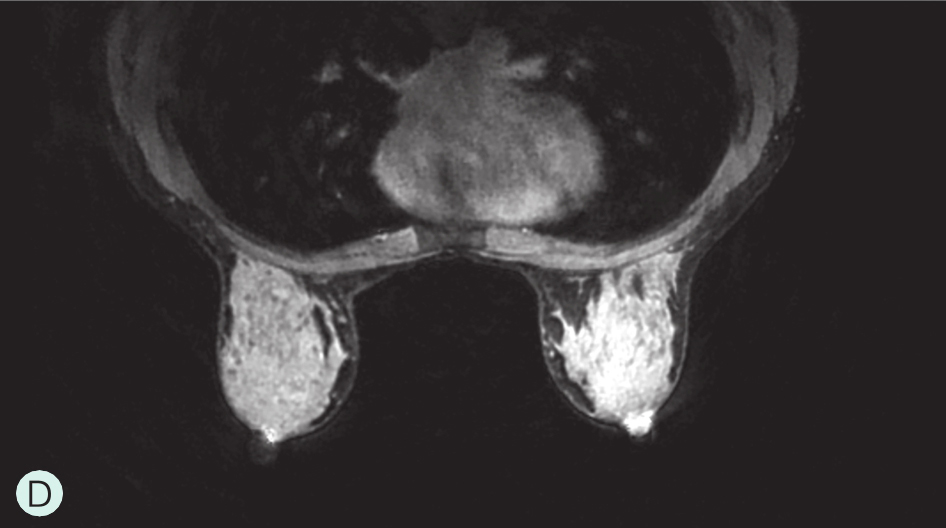

图1-3-3 乳腺MRI不同乳腺密度

A.脂肪型;B.散在致密型;C.不均匀致密型;D.极度致密型